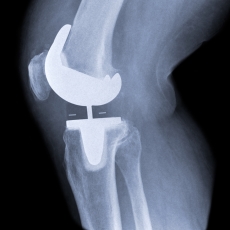

After removing the damaged knee cartilage and bone, the surgeon attaches the artificial parts to your bones. The artificial parts are made of metal and plastic. They will give your knee new, smooth surfaces.

Knee replacement surgery may replace all the damaged parts of your knee (total knee replacement) or just part of your knee (partial knee replacement). In a total knee replacement, the surgeon replaces 3 surfaces:

• The end of the shinbone

• The end of the thighbone

• The back of the kneecap